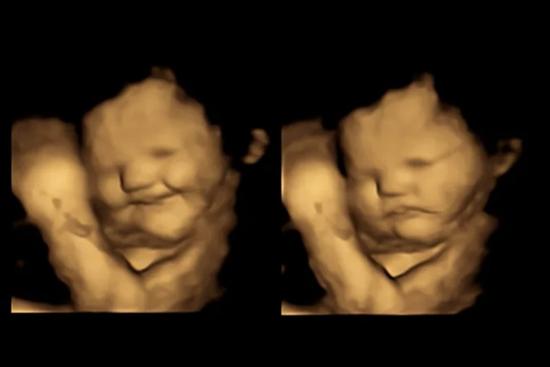

Thai nhi biểu hiện cảm xúc khác nhau khi mẹ ăn cà rốt và cải xoăn

Thai nhi trong bụng mẹ biểu hiện cau có sau khi mẹ ăn cải xoăn nhưng lại mỉm cười sau khi mẹ ăn cà rốt.